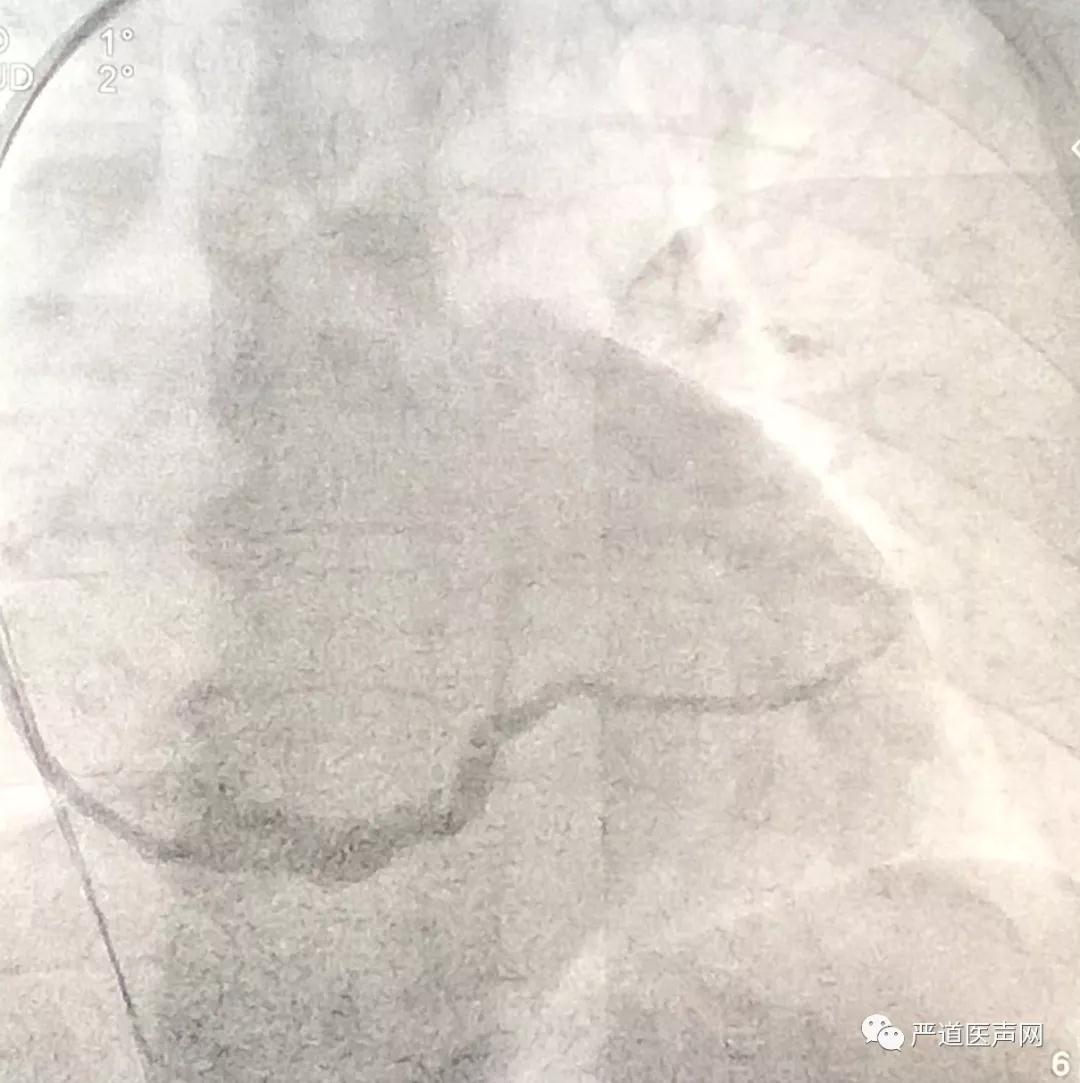

术前,严激教授为学员们分析了本例患者的病史特点,该患者存在扩张型心肌病,心电图提示LBBB,QRS波160ms,心超提示心脏增大,EF值24%,符合CRT-D植入的I类适应证。为了提高术后CRT的反应性,严激教授决定为该患者植入左室四极CRT-D,本例患者选用的是波士顿科学X4左室四极CRT-D。

术中造影

术中,严激教授为学员们讲解了CRT植入的标准操作步骤,对每一处需要注意的细节和操作要领进行了详细说明。本例患者的冠状窦开口部位存在一定阻力,为了增强外鞘管的推送力,严激教授采用EP导管寻找冠状窦并成功辅助外鞘管进入,静脉造影发现鞘管直接超选了患者的侧静脉,根据血管的走行情况,严激教授选择了波士顿科学ACUITY X4 Spiral S左室四极导线,这种导线具有远端叉齿和近端3D螺旋的双重固定设计,能够帮助导线更好的固定在血管远端。术中测试发现X4导线上四个电极的阈值均在正常范围内,无膈神经刺激出现。